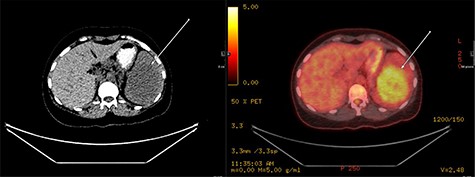

A repeat contrast-enhanced CT scan 21 months later showed an increase in size of the lesion to 8.0 × 7.2 × 6.6 cm (Fig. 4). Positron emission tomography (PET) CT demonstrated the mass to be moderately hypermetabolic with a standardized uptake value (SUV) of 4.7 (Fig. 5).

PET fused axial image with corresponding low-dose unenhanced CT image (left); the lesion is showing moderate FDG uptake (arrow).